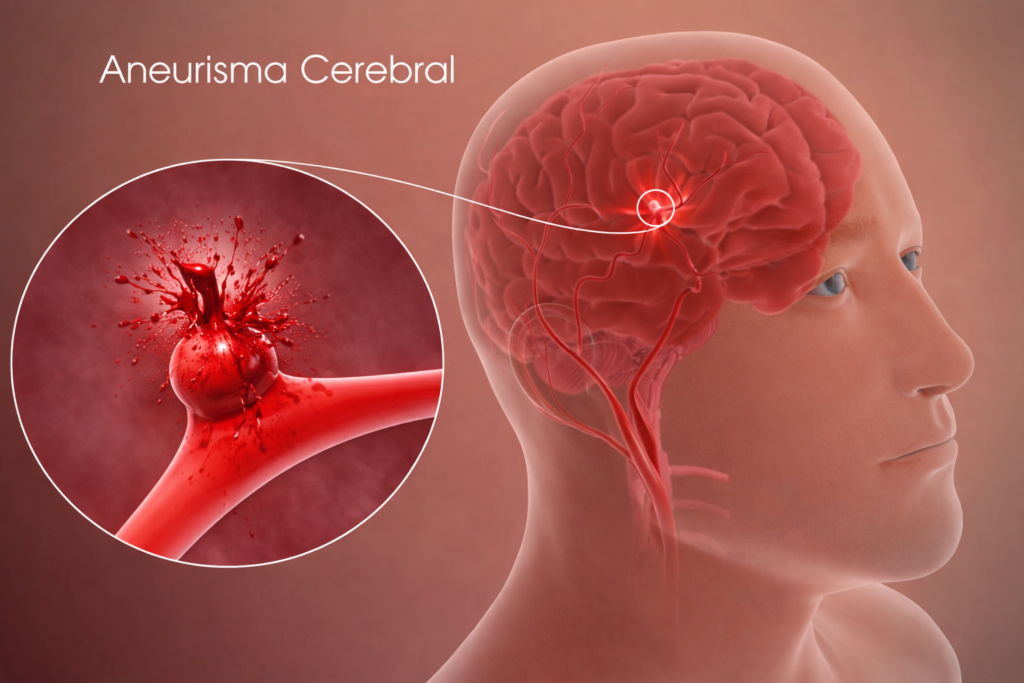

O que é aneurisma cerebral?

Um aneurisma cerebral é uma pequena “bolha” que se forma na parede de um vaso do cérebro. Essa parte da parede fica mais fina e mais frágil, como um ponto de fraqueza no encanamento.

A maior preocupação é o risco de rompimento, ou seja, de “estourar”. Quando isso acontece, pode causar um sangramento grave no cérebro e exige atendimento médico imediato.

Aneurisma roto x aneurisma não roto: qual é a diferença?

É quando existe uma parte mais fraca na parede do vaso do cérebro, que forma uma bolha, como se fosse uma bexiga ou um ponto frágil no cano.

Dizemos aneurisma não roto quando essa “bexiga” não estourou.

Aneurisma roto

É quando essa “bexiga” se rompe, ou seja, estoura, causando um sangramento dentro do cérebro.